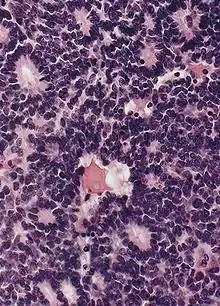

Flexner-Wintersteiner rosettes

- Tumor cells form Flexner-Wintersteiner rosettes